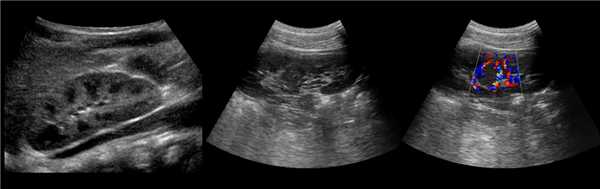

Рисунок. Дистальный отдел мочеточника расширен, в мочевом пузыре анэхогенное образование с тонким и ровным контуром — уретероцеле.

Рисунок. Двустороннее уретероцеле на УЗИ: в режиме ЦДК из верхушек уретероцеле определяется выброс мочи.